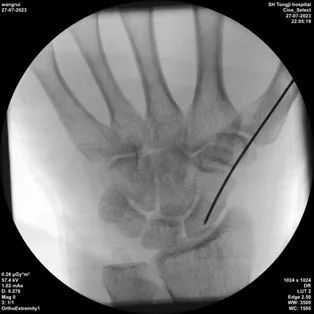

1、固定好3D打印的导板

2、沿导板上的孔打入导针,一次成功